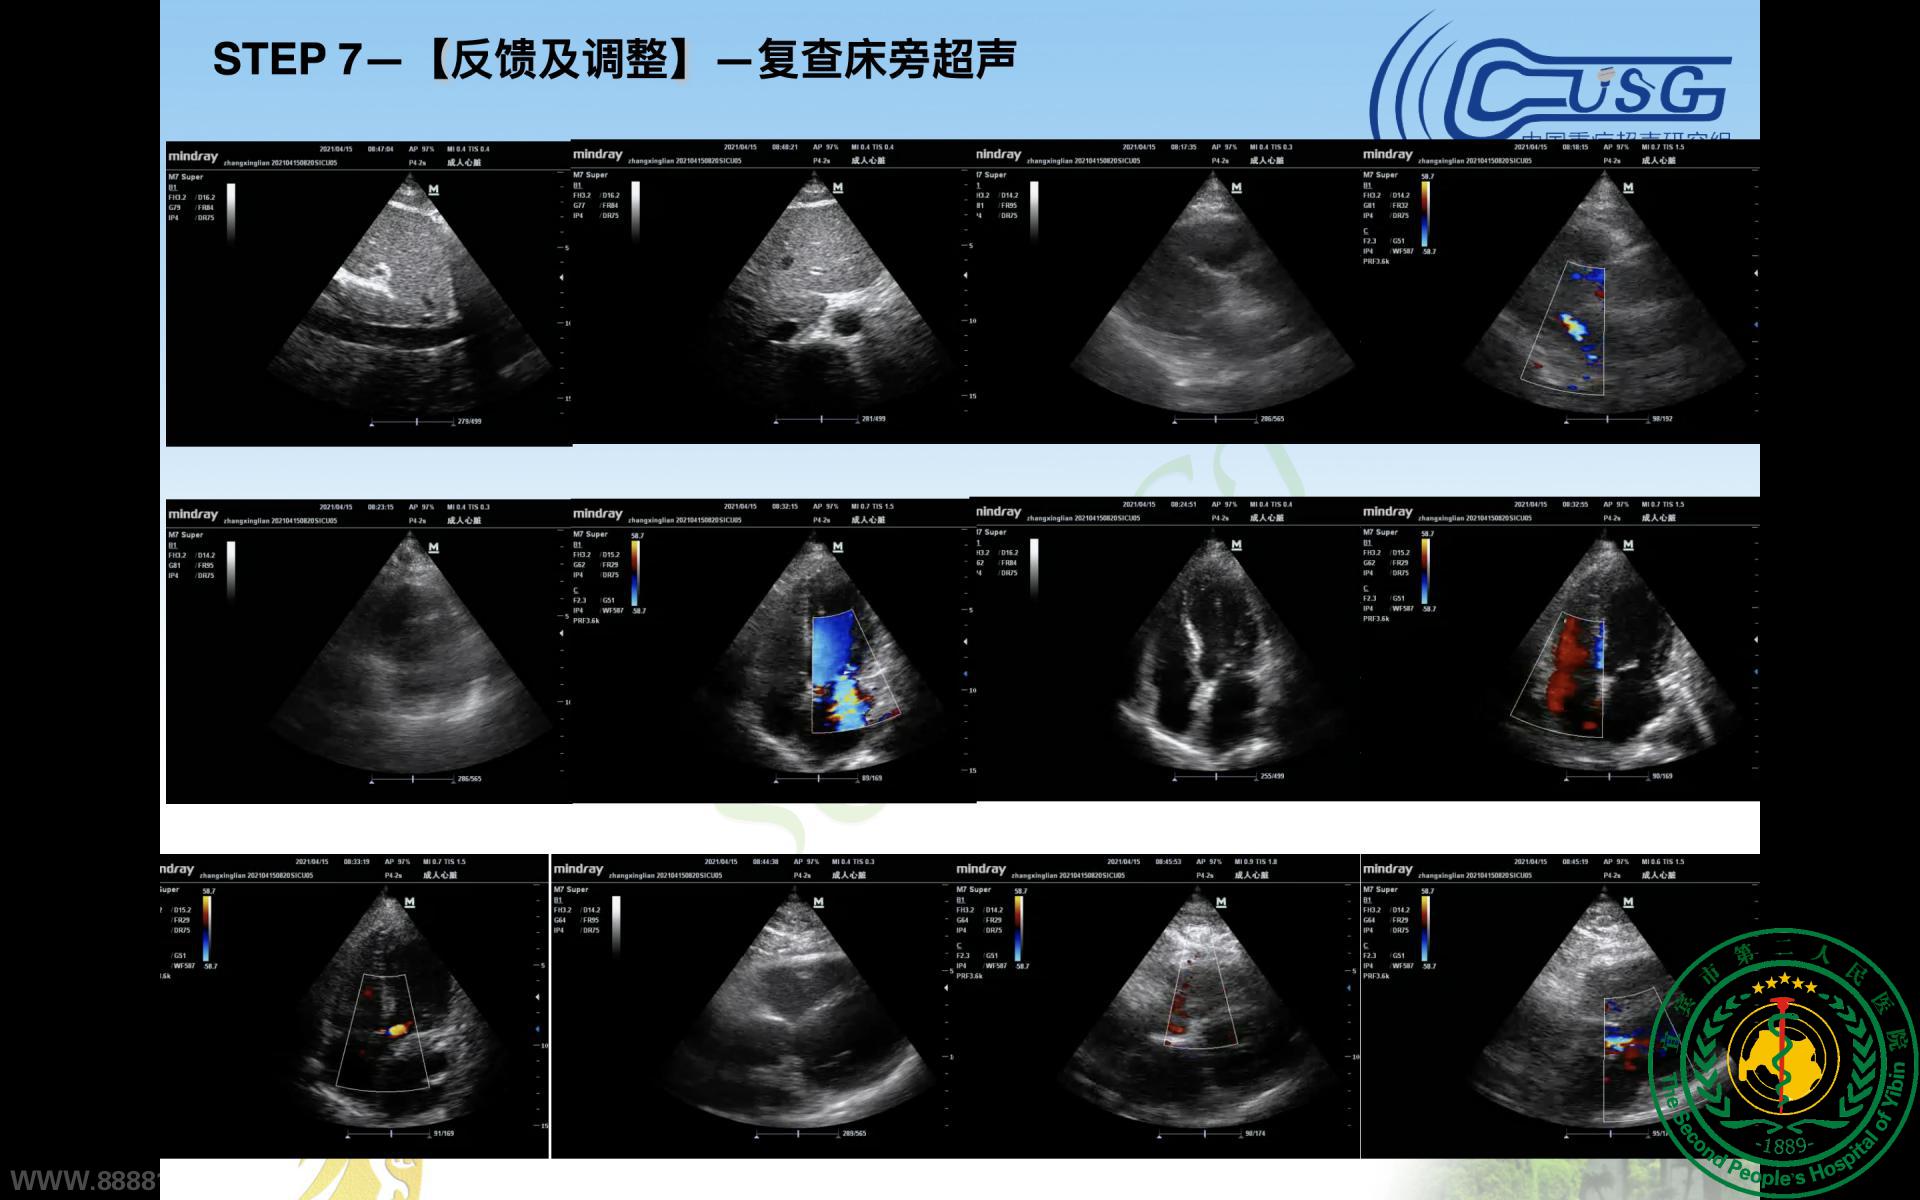

重症医学科协办四川省第十期重症超声培训会暨CCUSG重症超声巡回培训成都站基础班(宜宾分会场)圆满成功

重症医学科协办四川省第十期重症超声培训会暨CCUSG重症超声巡回培训成都站基础班(宜宾分会场)圆满成功35691